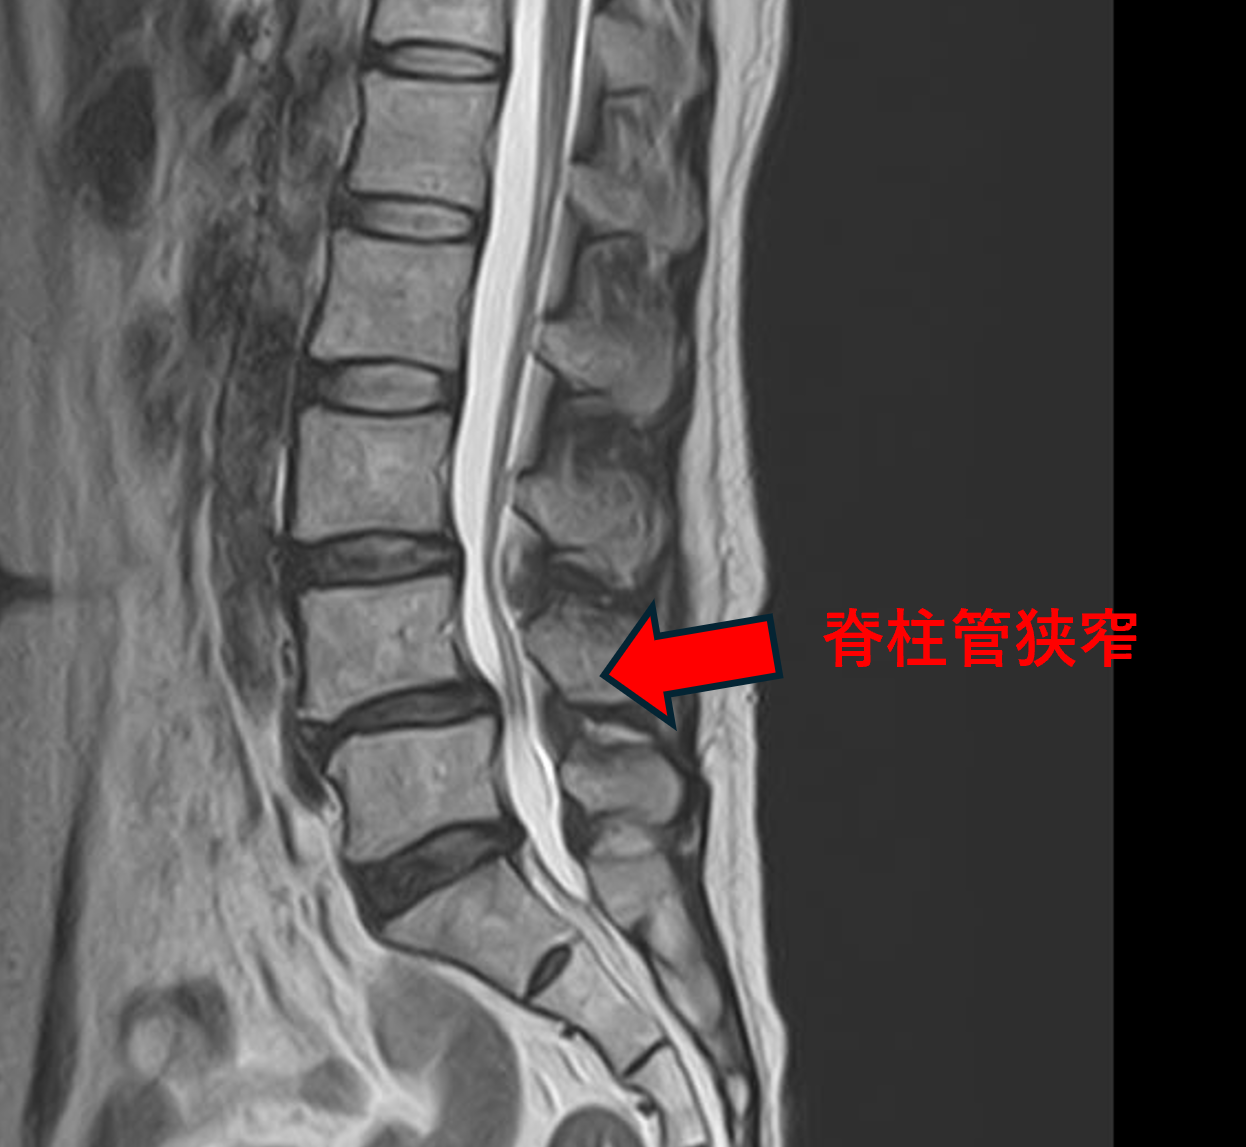

画像及び所見について

- L3/4、5/s – 椎間板変性、膨隆、椎間孔狭窄

- L4/5 – 椎間板変性、膨隆、椎間孔狭窄、脊柱管狭窄

以上のことが画像上認められました。

L3/4、4/5、5/sの椎間板所見による脊柱管の圧排が、症状の原因の可能性がもっとも高い。